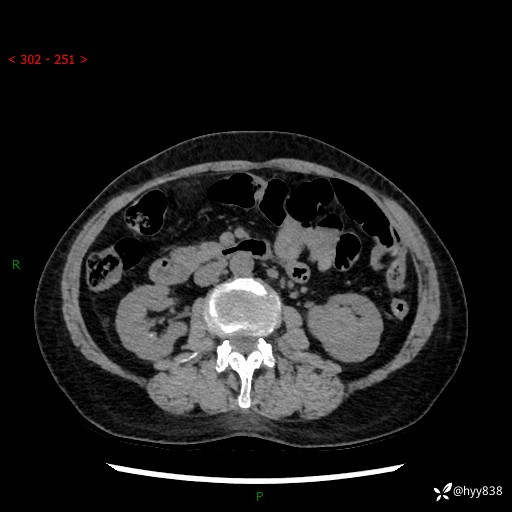

72岁/女,检查发现左肾占位1天。为了满足诊断,常规四期后,又加了延迟期-结果公布~

【患者信息】:72岁/女

【主诉】:检查发现左肾占位1天

【现病史及既往史】:患者于1天前检查发现左肾占位,无畏寒发热,无咳嗽咳痰,无腰腹部疼痛不适,无肉眼血尿、无尿频尿急症状,起病来,患者未行特殊治疗,为求进一步诊治,门诊以"左肾占位"收治入院。 发病来患者精神、饮食、睡眠良好,小便如上,大便正常,体重无明显变化。

【检查】:肾脏CT平扫+增强